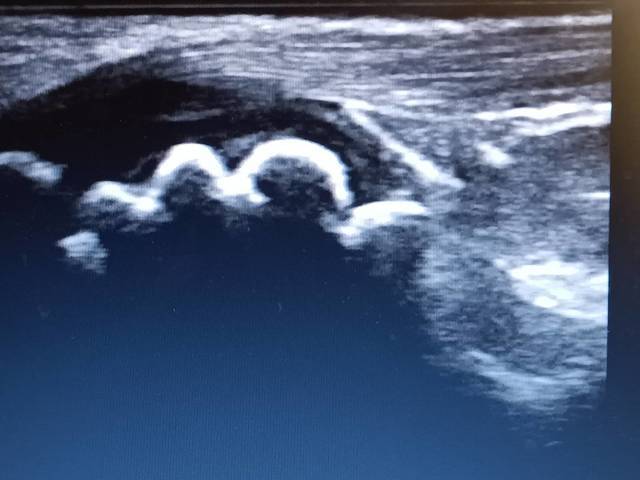

野球肩 肩前方の痛み

社会人野球 18歳女子 投手

投球時、また手を挙上すると、肩の前側が痛い。上腕二頭筋腱と大胸筋腱の損傷が考えられた。1回の施術で、楽になる様子です。